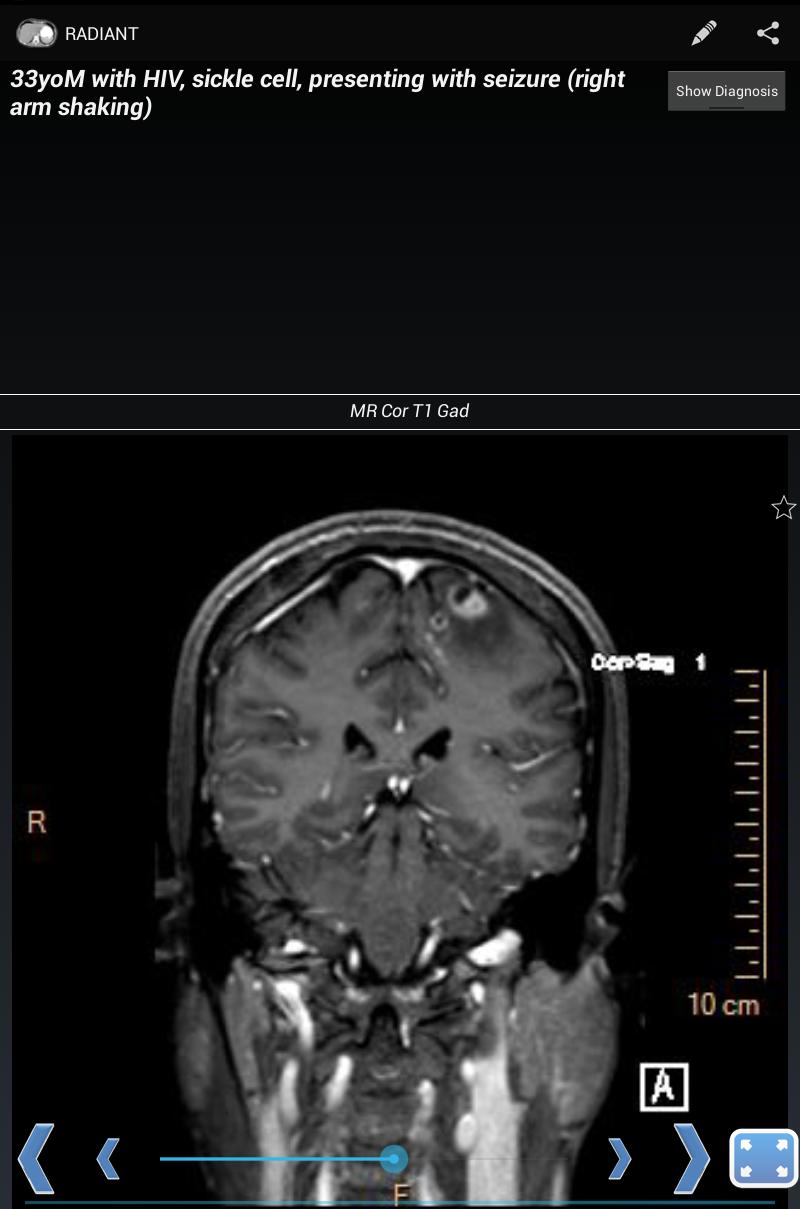

Radiant هو منصة لإنشاء وإدارة ومشاركة المواد التعليمية القائمة على الصور ، والتي تمثل في المقام الأول للمستخدمين في المجال الطبي. إنه مثالي لتبادل الحالات المثيرة للاهتمام بين سكان الأشعة التشخيصية والزملاء وطلاب الطب وأعضاء هيئة التدريس. لا يُقصد استخدامه للتشخيص.

يتم تنظيم المحتوى حول صورة واحدة كمكون أساسي. تشتمل الصور المتعددة ذات الصلة على سلسلة ، والتي تسمح بالتمرير عبر مكدس الصور. تشكل سلسلة الصور هذه اللبنات الأساسية للحالات (السلسلة ذات الصلة التي توضح نتائج التصوير لتشخيص محدد لدى مريض معين) ، وملفات تدريس (موضوعات منظمة في الفصول والفصل الفرعي مثل كتاب نصي) ، والاختبارات (أسئلة مرتبطة بسلسلة الصور المرتبطة). يمكن تجميع الحالات معًا في حزم الحالات ، والتي تستغرق فقط ثوانٍ لإنشاءها ، وهي مثالية لعروض الحالة غير المعروفة في اللحظة الأخيرة والدراسة.

مع Radiant ، يمكنك إنشاء حالات توضح الأشعة السينية أو الموجات فوق الصوتية أو التصوير المقطعي أو التصوير بالرنين المغناطيسي أو أي طريقة تصوير أخرى. إنها طريقة رائعة لتعلم الأشعة السينية للصدر ، والتشريح الطبيعي ، وعمليات المرض الشائعة ، باستخدام صور طبية تشخيصية حقيقية وعالية الجودة.